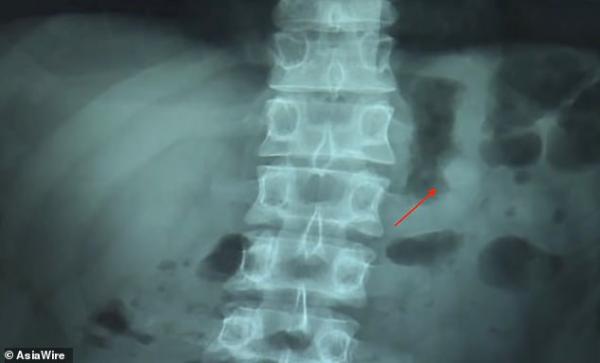

Τα ακουστικά συνέχισαν να λειτουργούν τόσο μέσα στο στομάχι του, όσο και αφού τα απέβαλε ο οργανισμός του.